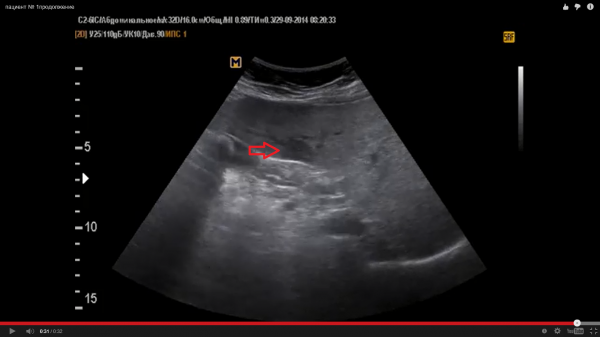

Пациентов - два. № 1 - женщина 60 лет № 2- мужчина 50 лет

Согласен. Очень часто встречается,особенно, в IV сегменте.Это могут быть не измененные участки на фоне диффузных изменений паренхимы печени (таких как жировой гепатоз).

Тоже соглашусь с версией, что это очаги сохраненной ткани печени на фоне жирового гепатоза. Часто такое встречается возле желчного пузыря и вдоль крупных сосудистых ветвей!

Я тоже за жировой гепатоз с нормальным участком паренхимы печени. Но определение гипостеатоза встречаю в первые, разве так называют нормальную печёночную ткань в данной ситуации?